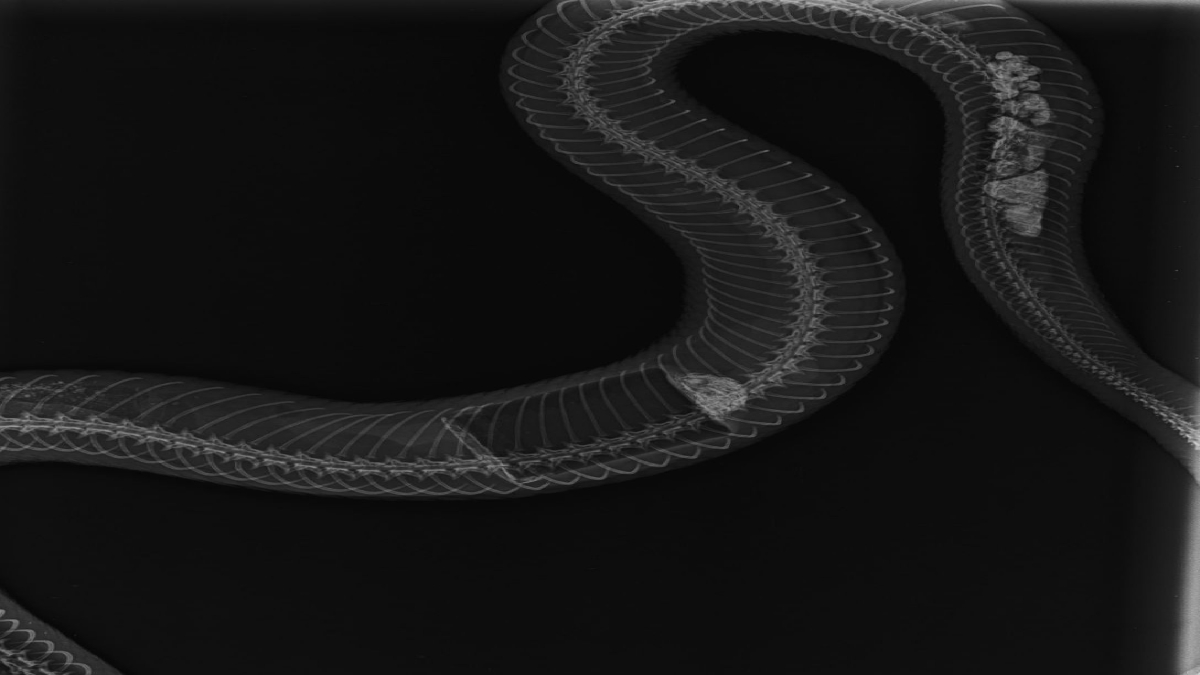

ಗಾಯಕ್ಕೆ ಚಿಕಿತ್ಸೆ ಒದಗಿಸಿದ ವೈದ್ಯರು ಹಾವಿನ ಹೊಟ್ಟೆ ಉಬ್ಬೇರಿದ್ದು ಗಮನಿಸಿ ಎಕ್ಸ್ ರೇ ಮಾಡುತ್ತಾರೆ. ಆಗ ಅದರ ಉದರದೊಳಗೆ ಪ್ಲಾಸ್ಟಿಕ್ ವಸ್ತುವಿರುವುದು ಗಮನಕ್ಕೆ ಬರುತ್ತದೆ. ಆದ್ದರಿಂದ ಹಾವಿಗೆ ಶಸ್ತ್ರಚಿಕಿತ್ಸೆ ನಡೆಸಿ ಉದರದೊಳಗಿದ್ದ ಸುಣ್ಣದ ಪ್ಲಾಸ್ಟಿಕ್ ಡಬ್ಬವನ್ನು ಯಶಸ್ವಿಯಾಗಿ ಹೊರತೆಗೆಯಲಾಗುತ್ತದೆ.

ಡಾ.ಯಶಸ್ವಿಯವರ ಪ್ರಕಾರ 'ಸುಮಾರು ಐದು ಅಡಿ ಉದ್ದದ ಸಾಕಷ್ಟು ದಪ್ಪವೂ ಇದ್ದ ಹೆಣ್ಣು ನಾಗರಹಾವು ಇದಾಗಿತ್ತು. 10ವರ್ಷ ಪ್ರಾಯವಾಗಿರಬಹುದು. ಹಾವು ಮೊಟ್ಟೆ ನುಂಗುವ ವೇಳೆ ಸುಣ್ಣದ ಡಬ್ಬವನ್ನು ಒಟ್ಟಿಗೆ ನುಂಗಿದ್ದಿರಬಹುದು' ಎಂದು ಶಂಕೆ ವ್ಯಕ್ತಪಡಿಸಿದ್ದಾರೆ.